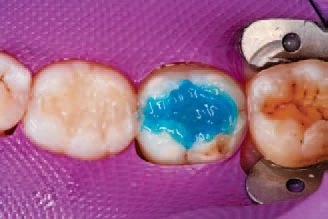

Preparation then began on tooth No. 31. Ivoclar Vivadent’s Total Etch was applied to the enamel and allowed to penetrate for 15 seconds, after which the etchant was applied to the dentin and allowed to penetrate for 10 seconds to ensure proper etching of both surfaces (Figs. 14 and 15). The etchant was then rinsed off with water, and all excess moisture was removed.